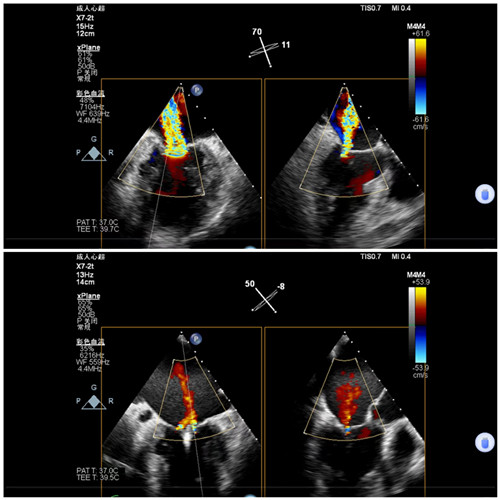

手术前后二尖瓣反流

7月9日上午,心内科联合麻醉科、胸外科等多学科,共同为陈奶奶开展手术,术前二尖瓣大量反流,反流程度5+,肺静脉反流明显,术后二尖瓣少量反流,反流程度1+,肺静脉反流消失,手术顺利结束。术后安返病房,次日陈奶奶从不能平卧到能下床活动。在医护人员的精心照顾下,陈奶奶现已顺利出院。